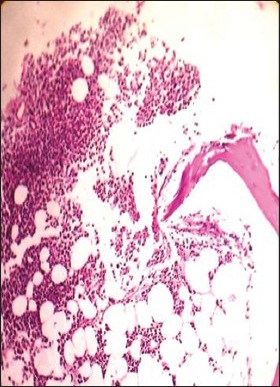

The clinicopathologic characteristics of all 14 patients with MM (13 newly diagnosed, 1 relapsed) are presented in Table 1. There were 11 males and 3 females with age range of 38-81 years (mean = 54 years, standard deviation = 10.7); and all were symptomatic at the time of evaluation. Eight (57%) were in Durie and Salmon Stage II, 5 (37%) Stage III and 1 (7%) in Stage I. Out of 14 cases, 10 (71.5%) presented with advanced lytic bone lesions, and two had organomegaly (one of which was de novo plasma cell leukemia). All, except one, had demonstrable light chain restriction (7 ‘ĸ’, 6 ‘λ’) by either IHC or biochemical assay techniques. Corrected serum calcium was found to be within normal range (≤11 mg/dL) in the majority of patients. On bone marrow evaluation, 10/14 (71%) cases showed an interstitial pattern of infiltration with or without focal nodularity; and 4 (29%) had packed marrow (diffuse pattern). Out of 14 cases, 10 (71%) cases were in Bartl's histologic Stage III (>50% tumor cells); and in 7 (50%), myeloma cells exhibited a high grade (blastic or pleomorphic) phenotype. Intracytoplasmic (Russell bodies) and intranuclear (Dutcher bodies) were noted in 11/13 patients; and in two intracytoplasmic crystalline inclusions were seen [Figures [Figures1a1a–g].

| Fig. 1d Hematoxylin and eosin stained bone marrow trephine sections showing interstitial pattern of infiltration by myeloma cells (×400)